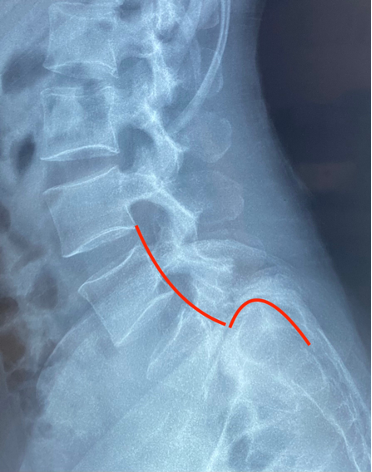

Sau khi tìm hiểu đi thăm khám kiểm tra ở nhiều nơi, chị quyết định đến khám và điều trị tại Bệnh viện Hoàn Mỹ ITO Đồng Nai. Kết quả chụp Cộng hưởng từ (MRI) và X-quang cột sống thắt lưng cho thấy chị bị trượt thân L5 ra trước độ IV - mức độ tổn thương nghiêm trọng của cột sống là mức cao nhất và nguy hiểm nhất của bệnh lý trượt cột sống. Nếu không can thiệp phẫu thuật có thể gây ra những biến chứng nghiêm trọng đến sức khỏe của người bệnh như yếu liệt hai bàn chân, thậm chí rối loạn tiểu tiện.

Đốt sống L5 trượt ra trước độ IV trên phim MRI